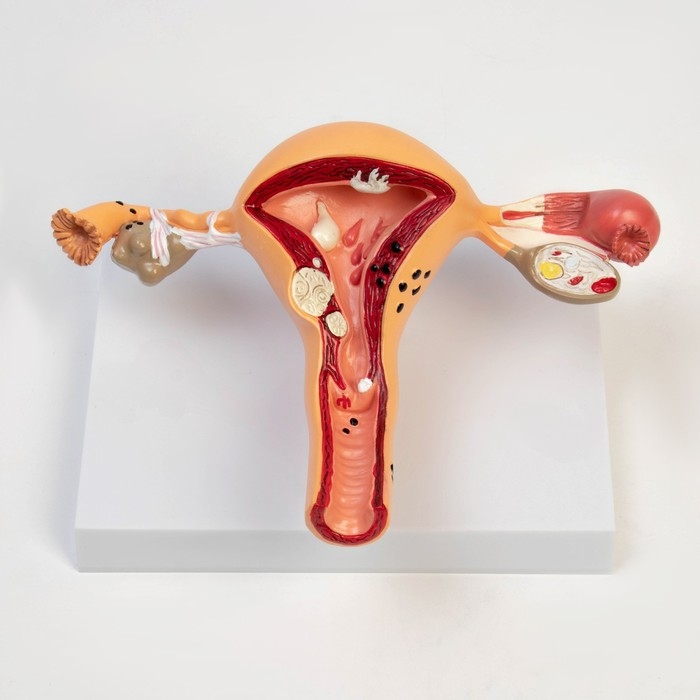

ЕКБ 167

No Brand, артикул: 7072352